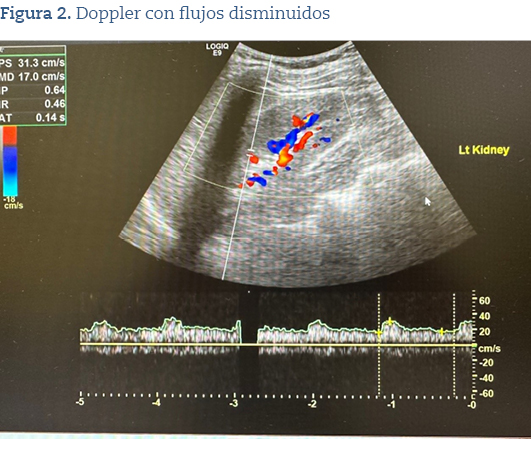

En la ecografía, se objetivó tamaño de ambos riñones normales sin presencia de quistes o nódulos (figura 1), pero en el Doppler (figura 2) se apreciaban flujos disminuidos en ambos riñones.

Ante tales resultados, se derivó al paciente al servicio de nefrología, donde se solicitaron nuevos parámetros analíticos y se citó al paciente para hacerle una angiotomografía computarizada (angio-TC) de arterias renales ante la persistencia de flujos disminuidos en los riñones.

La prueba de imagen inicial puede ser la ecografía y Doppler de arterias renales, recurso al alcance de Atención Primaria, y ampliarlo a angio-TC de arterias renales, si el resultado ecográfico resulta negativo1,2.